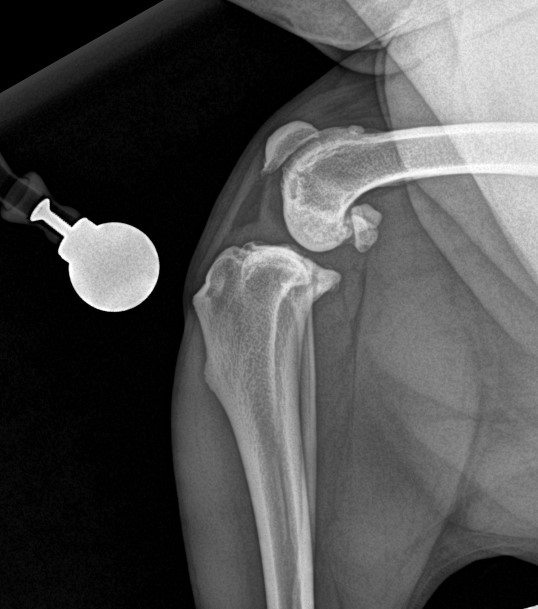

TPLO Pre Op